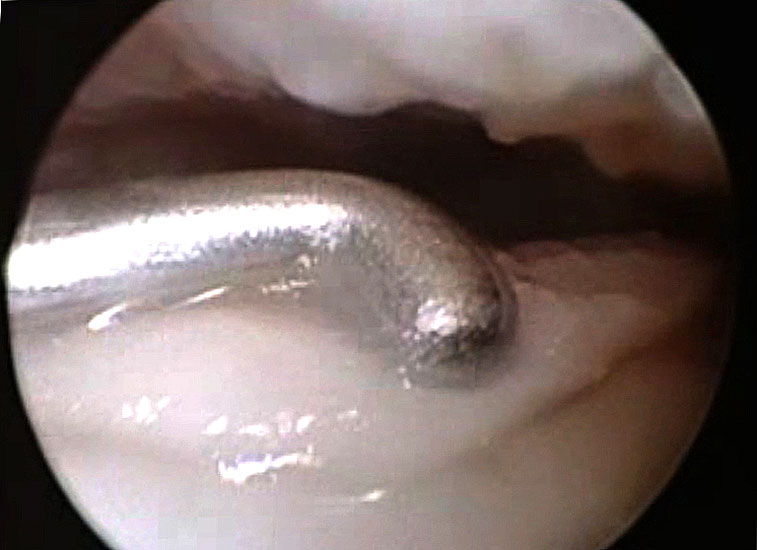

Die arthroskopische Diagnostik bietet gegenüber den rein bildgebenden Methoden den Vorteil, dass der Defektbereich auch mit einem Tasthaken palpatorisch untersucht werden kann. Dadurch kann die Defektgröße bestimmt und eine evtl. Instabilität eines osteochondralen Fragmentes festgestellt werden 28. Der Nachteil ist dabei allerdings, dass eine genaue Beurteilung des subchondralen Knochens nur bedingt erfolgen kann.

Bei chondralen Läsionen III-IV° oder bei osteochondralen Läsionen (≥ Stadium 2) mit Kontinuitätsunterbrechung der Knorpeloberfläche und Instabilität des Fragmentes (Abb. 11), besteht in der Regel die Indikation zum Debridement und Kürettage der Läsion und Anwendung von knochenmarkstimulierenden Techniken wie der Anbohrung oder Mikrofrakturierung. Durch die chirurgische Eröffnung des subchondralen Knochens sollen über die gesetzten Blutungsherde pluripotente mesenchymale Stammzellen in die Defektzone gelangen und einen Reparaturprozess einleiten 52. Ziel ist die Bildung eines möglichst belastungsstabilen Ersatzknorpelgewebes. Das arthroskopische Vorgehen mit Knochenmarkstimulation stellt nach einem Expertenkonsensus während der „Conference of the International Society of Arthroscopy, Knee Surgery and Orthopaedic Sports Medicine and International Federation of Sports Medicine (ISAKOS—FIMS)” aus dem Jahre 2005 für die meisten Fälle die Methode der ersten Wahl dar 39. Bevorzugt wird heute meist die Mikrofrakturierung, bei der rein arthroskopisch nach Stabilisierung der Läsion mit Schaffung intakter Knorpelkanten mit verschieden abgewinkelten Ahlen multiple Löcher unter Erhalt von Knochenbrücken in das Defektbett geschlagen (Abb. 12 und 13) und so eine Verbindungen zum spongiösen Knochen hergestellt wird. In der Regel können die Läsionen mit den arthroskopischen Standardportalen behandelt werden 5354. Orientierend kann bei der Planung und physiologischer uneingeschränkter Plantarflexionsmöglichkeit angenommen werden, dass neben den anterioren Defekten auch Läsionen, welche die vordere Hälfte des posterioren Anteil des Talus betreffen, erreicht und rein arthroskopisch behandelt werden können 39. Im Zweifelsfall kann eine Bildgebung in maximaler Plantarflexion weitere Hinweise geben.